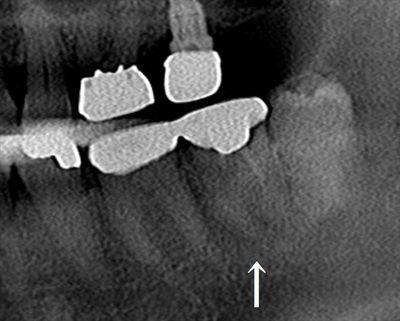

矢印の左下第二大臼歯の金属を除去し、再根管治療を行います。

画像右隣の左下親知らずは抜歯予定です。